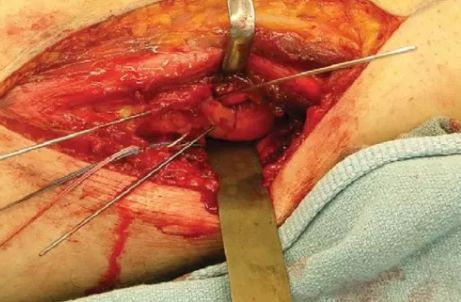

影像诊断:部分Hoffa骨折X线片不能提供明确的诊断,漏诊率较高。需要CT或MRI检查,并根据患者的病史、查体及影像学检查予以确诊。

部分Hoffa骨折普通X光片易漏诊

CT扫描在矢状位、轴位容易发现骨折及骨折线的走形方向

关节镜微创入路

关节镜微创手术可减少软组织剥离和出血量,术后关节功能及软组织恢复较好。但目前仅有少数个案报道,尚并无充分证据支持关节镜辅助Hoffa骨折。